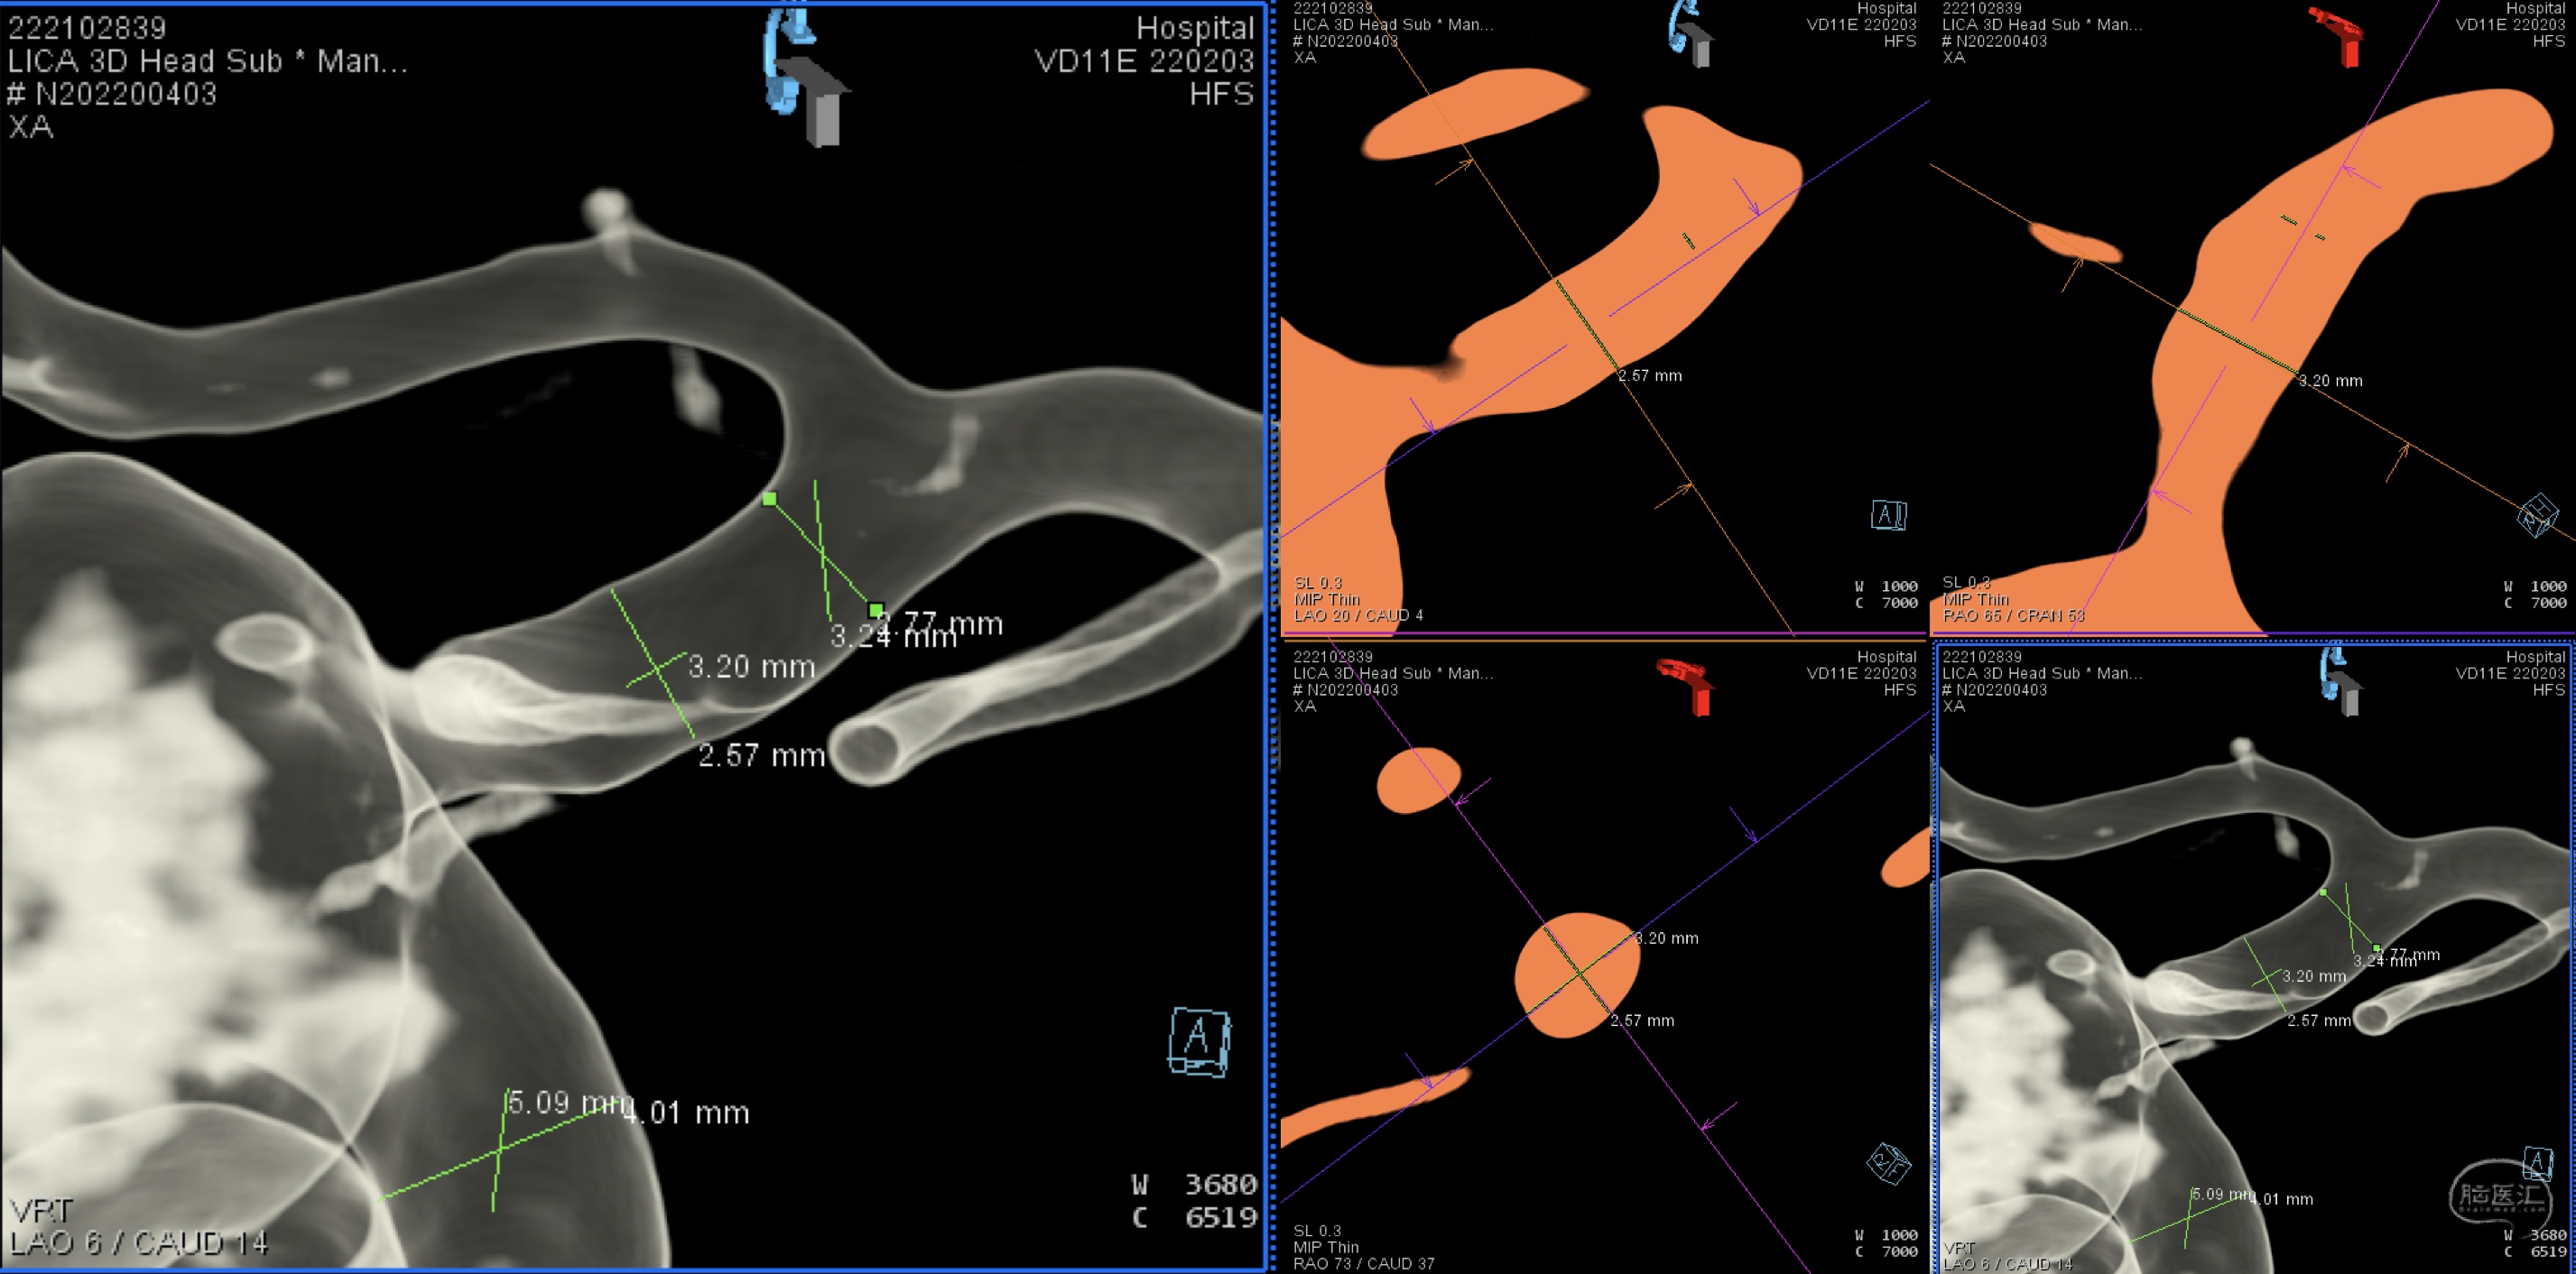

详细测量载瘤动脉远近段动脉直径。

详细测量载瘤动脉远近段动脉直径。

最终选择Surpass Streamlin 4*50mm支架。